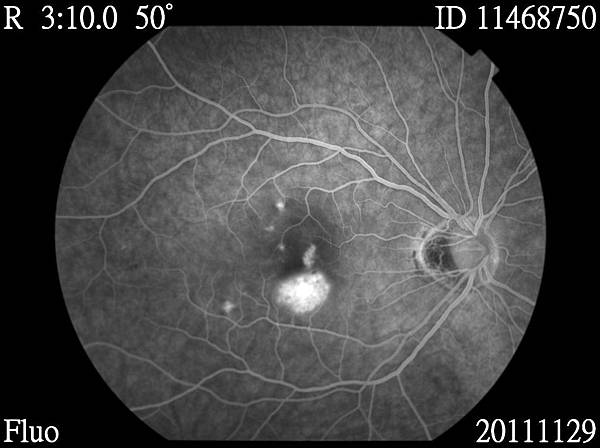

11468750_20111129_142518_Redfree_R_001.JPG 11468750_20111129_142737_Fluo_R_001.JPG 11468750_20111129_142746_Fluo_R_001.JPG 11468750_20111129_142954_Fluo_R_001.JPG 11468750_20111129_143002_Fluo_R_001.JPG 11468750_20111129_143009_Fluo_R_001.JPG 11468750_20111129_143031_Fluo_R_001.JPG 11468750_20111129_143749_Fluo_R_001.JPG 11468750_20111129_143818_Fluo_R_001.JPG

醫生說,我的黃斑部新生血管,需要眼內注射藥物去抑制他繼續增生,還有,視網膜周圍變薄了,需要先做雷射把他圍起來,避免將來破掉.....

至於新生血管的部份,要再做脈絡膜的檢查...因為我不只新生血管,旁邊還有好幾個點,這是比較奇怪的....